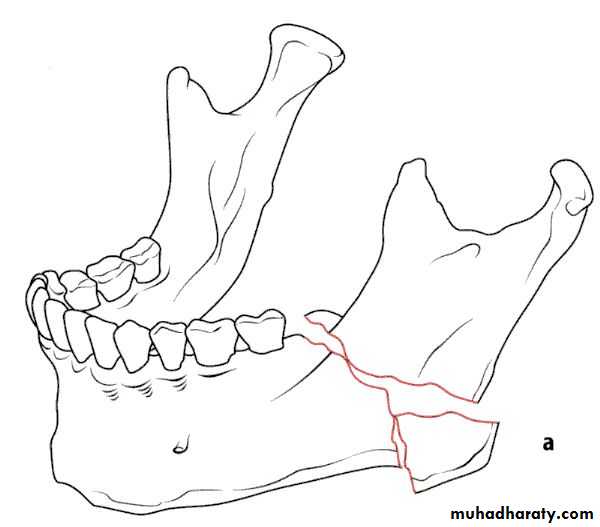

Class 34-classification according to the Direction of the fracture and favourability for the treatment

1- Horizontally favorable fracture.

2- Horizontally unfavorable fracture.

When the muscle pull resist fracture displacement , it is favorable(undisplaced), but, when the muscle pull distract the fragments away from each other resulting in displacement , it is unfavorable.

• Horizontally unfavorable fracture extends from the upper border downwards and backwards.

• Horizontally favorable fracture extend from upper border downwards and forwards.